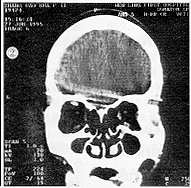

冠状位上水平肌垂直,几乎平衡,上直肌向外向上倾斜,下直肌相反,向下向外。视神经为圆形显影,位置偏内、偏上(图2)。眶尖至球后壁间眼眶形态极不规则,当切面移至球后壁时,才变得较圆和眼球形态相仿。